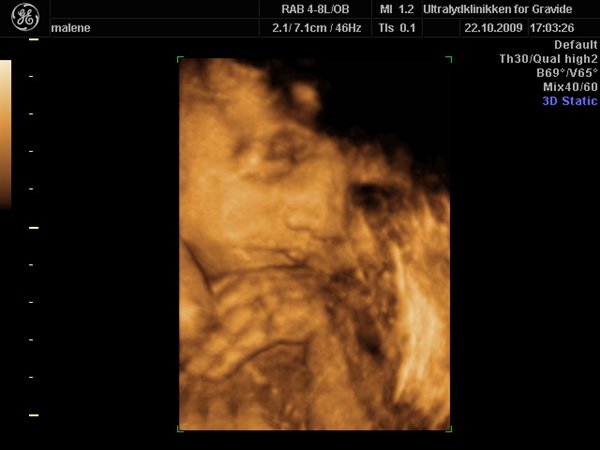

Jeg havde egentlig besluttet fra start af at jeg ville bestemt ikke smide penge efter en 3D scanning, men må indrømme jeg blev fristet

Så vi fik en hurtig tid i eftermiddags, og kom op og vinke lidt til den lille meget stædige prinsesse som vi så fint bekræftet hun er

Hun har allerede nu en masse hår på hovedet, og ligger meget dybt i bækkenet, så det var ikke muligt at få hele hovedet med, da man jo ikke kan scanne igennem knogler.

Hun var lige som hun skulle være, og vejer 1200 g

Vedhæftede fotos (klik for at se i fuld størrelse)